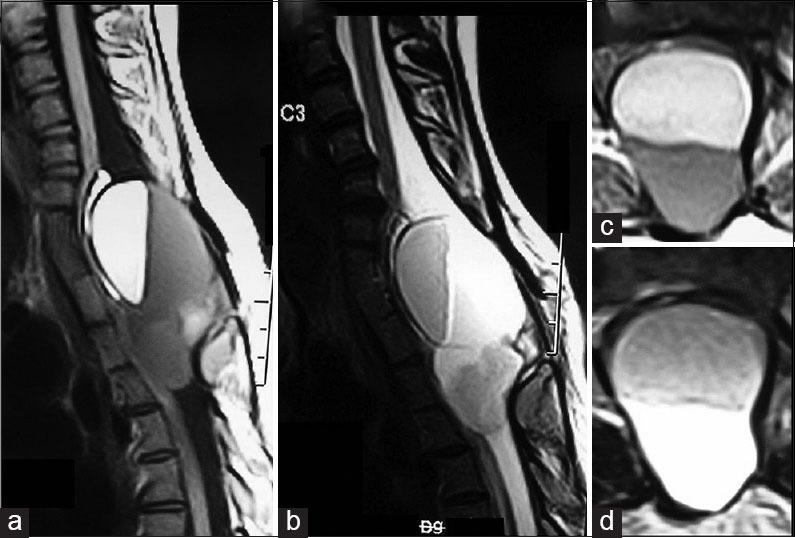

Infected cervico-dorsal dermoid cyst with fluid - fluid level.

We report a case of a 22-year-old female who was operated at the age of 3 months for cervico-dorsal swelling. She presented with gradual onset, progressively worsening dull aching pain in the cervico-dorsal region, 21 years following previous surgery. Magnetic resonance imaging showed intradural dermoid cyst with the fluid level. She underwent excision of the dermoid cyst with excision of the wall. The clinical profile, etiopathogenesis, radiological features, and management of intraspinal dermoid cysts are discussed in the light of current literature.

我们报告一例22岁女性病例,该患者3个月大时因颈背部肿胀接受手术。在先前手术21年后,她出现颈背部区域逐渐起病、逐渐加重的钝痛。磁共振成像显示硬膜内有液平面的皮样囊肿。她接受了皮样囊肿切除及囊壁切除术。本文结合当前文献对脊髓皮样囊肿的临床特征、病因发病机制、放射学特征及治疗进行了讨论。